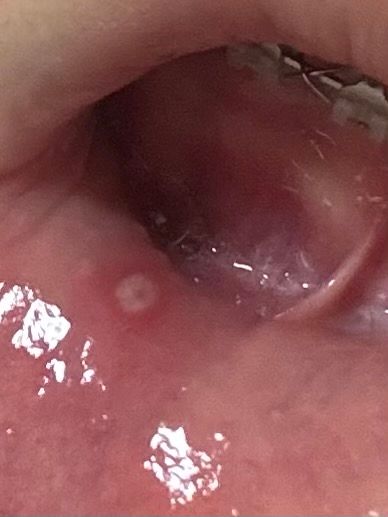

교정기 때문에 구내염이 생겼는데 어떤 약이 좋나요?

제목 그대론데 교정을 하면서 이가 움직여서 입술이랑 교정기에 마찰 때문에 생긴 거 같은데 무슨 약을 발라야 금방 나을까요? 그리고 교정기에 입술이 계속 쓸리면 어떻게 대처해야 하나요?ㅠㅠ

• 1번 째 사진

교정장치가 지속적으로 잇몸을 자극하거나 구강 점막을 자극할 경우 해당부에 구니염이 생길 수 있습니다. 이렇게 구내염이 생겼을 때는 자극을 하는 장치물의 교정용 왁스 등을 사용해 주는 것이 좋습니다. 또한 구내염이 있는 부위에는 오라매니 등을 도포해준다면 통증을 줄일 수도 있습니다.

약국에 가셔서 구내염에 바르는 약을 구매 하셔서 바르시면될것같습니다 침때문에 잘 씻겨 내려가니 자주 도포를 해주세요.

제목 그대론데 교정을 하면서 이가 움직여서 입술이랑 교정기에 마찰 때문에 생긴 거 같은데 무슨 약을 발라야 금방 나을까요? -> 오라메디 바르세요

그리고 교정기에 입술이 계속 쓸리면 어떻게 대처해야 하나요?ㅠㅠ -> 날카로운 부분은 레진볼,왁스를 붙여줍니다